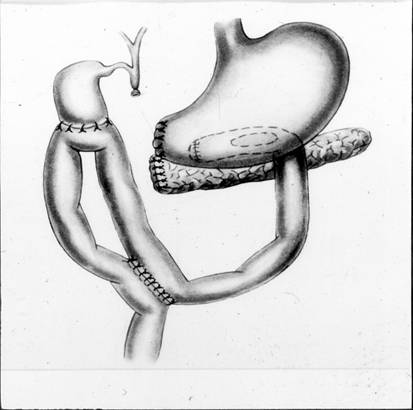

n 3 МЕСЯЦА-- ГОД - ВНУТРЕННЕЕ ДРЕНИРОВАНИЕ (ЦИСТО-ЭНТЕРО, ЦИСТОГАСТРОАНАСТОМОЗ)

n МИНИИНВАЗИВНОЕ ДРЕНИРОВАНИЕ И СКЛЕРОХИРУРГИЯ